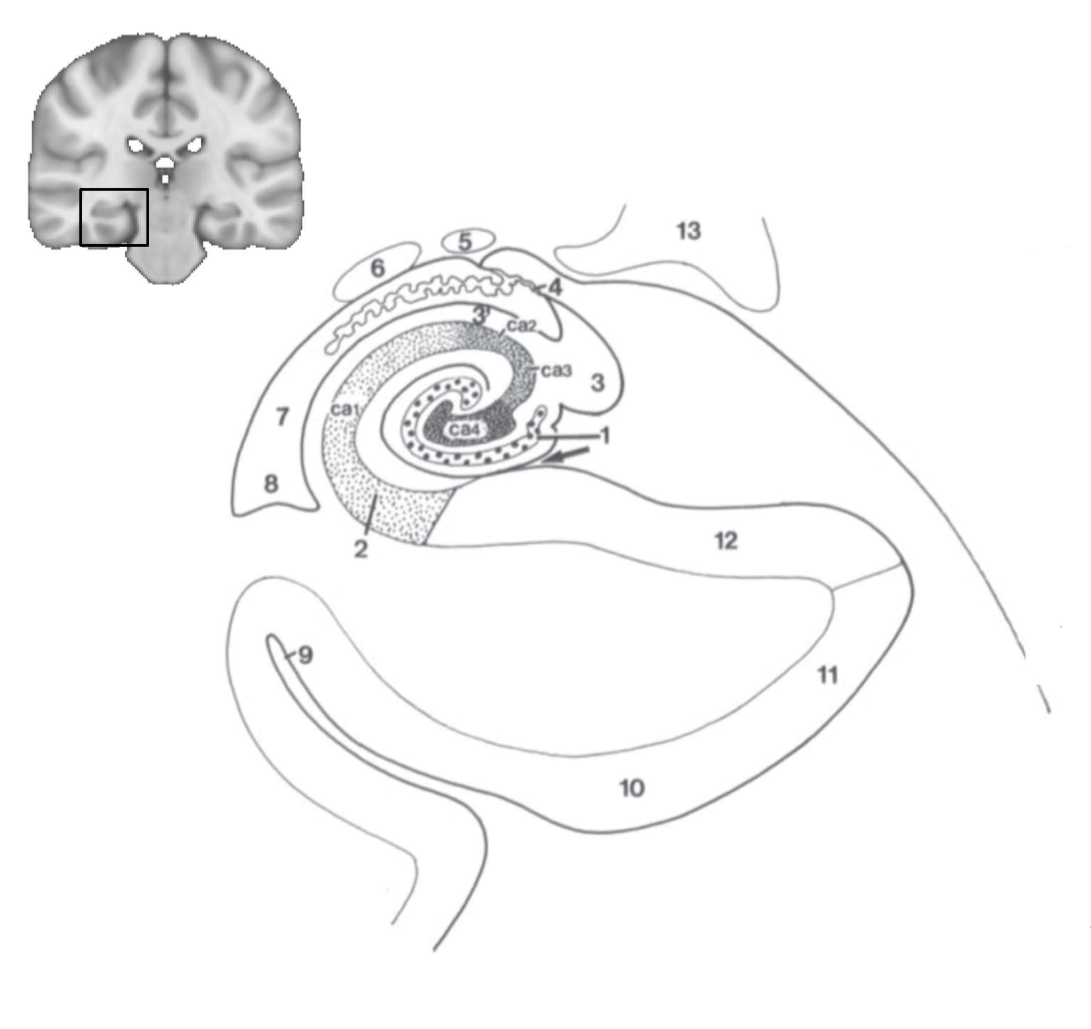

What structure is this?

hippocampus

What is 1?

hippocampus

What is 2?

rhinal sulcus

What is 3?

lateral ventricle

What is 4?

thalamus

What is 5?

entorhinal cortex

What is 6?

perirhinal cortex

What is 7?

parahippocampal cortex

What is 1?

gyrus dentatus

What is 2?

cornu ammonis

What is 3?

fimbria

What is 3’?

alveus

What is the arrow pointing to?

happicampal sulcus

What is ca1, ca2, ca3 and ca4?

fields of cornu ammonis

What is 4?

tela choroidea

What is 5?

stria terminalis

What is 6?

tail of caudate nucleus

What is 7?

temporal horn of lateral ventricle

What is 8?

collateral eminence

What is 9?

collateral sulcus

What is 10?

parahippocampal

What is 11?

entorhinal area

What is 12?

subiculum

What is 13?

lateral geniculate body